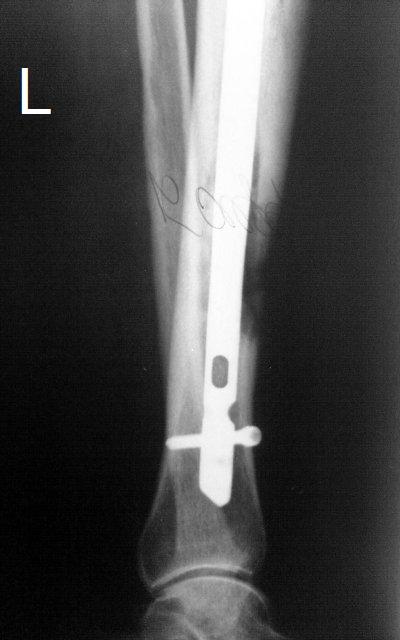

Итак, в настоящий момент больной пришел к нам с полной нагрузкой на оперированную конечность и с такой картиной

(см. приложение). Участок мягких тканей, с передней стенкой  нижней трети ББК, выгнил и представляет дефект

2×2,5 см. На перевязке - циркулярный(?) некроз костной трубки.

-----------   -----------

Вложение не в текстовом формате было извлечено…

Имя     : tibLAT00.JPG

Тип     : image/jpeg

Размер  : 30885 байтов

Описание: отсутствует

Url     : http://weborto.net:8080/pipermail/ortho/attachments/20091123/dddb0a2c/attachment-0015.jpeg